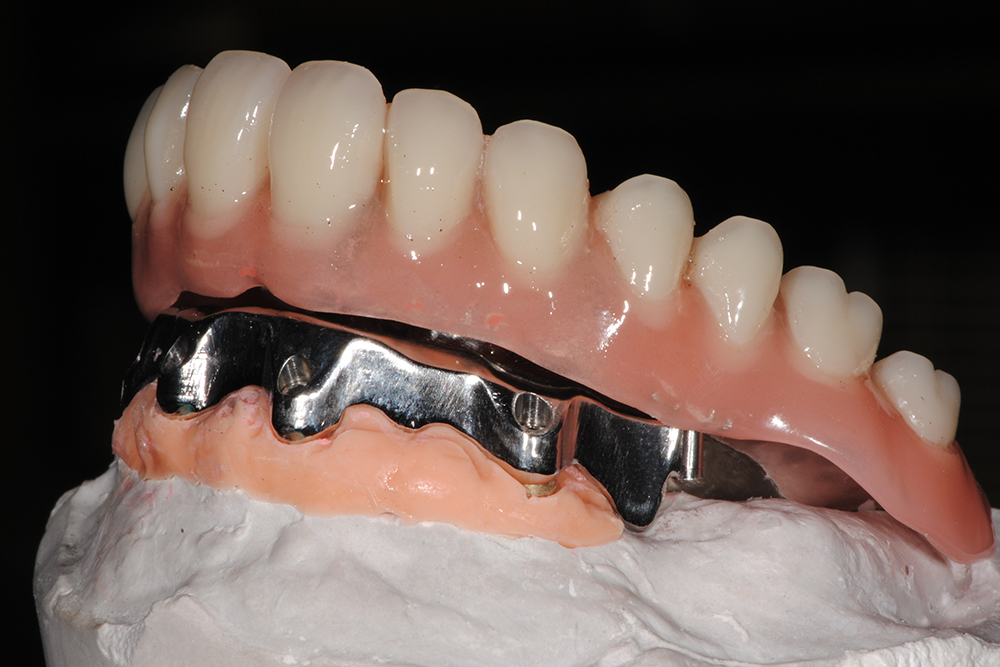

Ripristino dell’arcata superiore su overdenture su barra